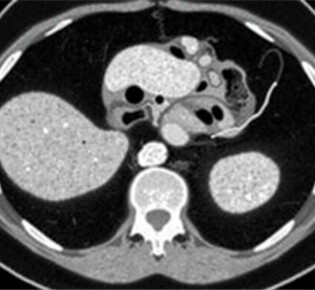

Radiology Corner: Cómo identificar la apendicitis en una tomografía computarizada